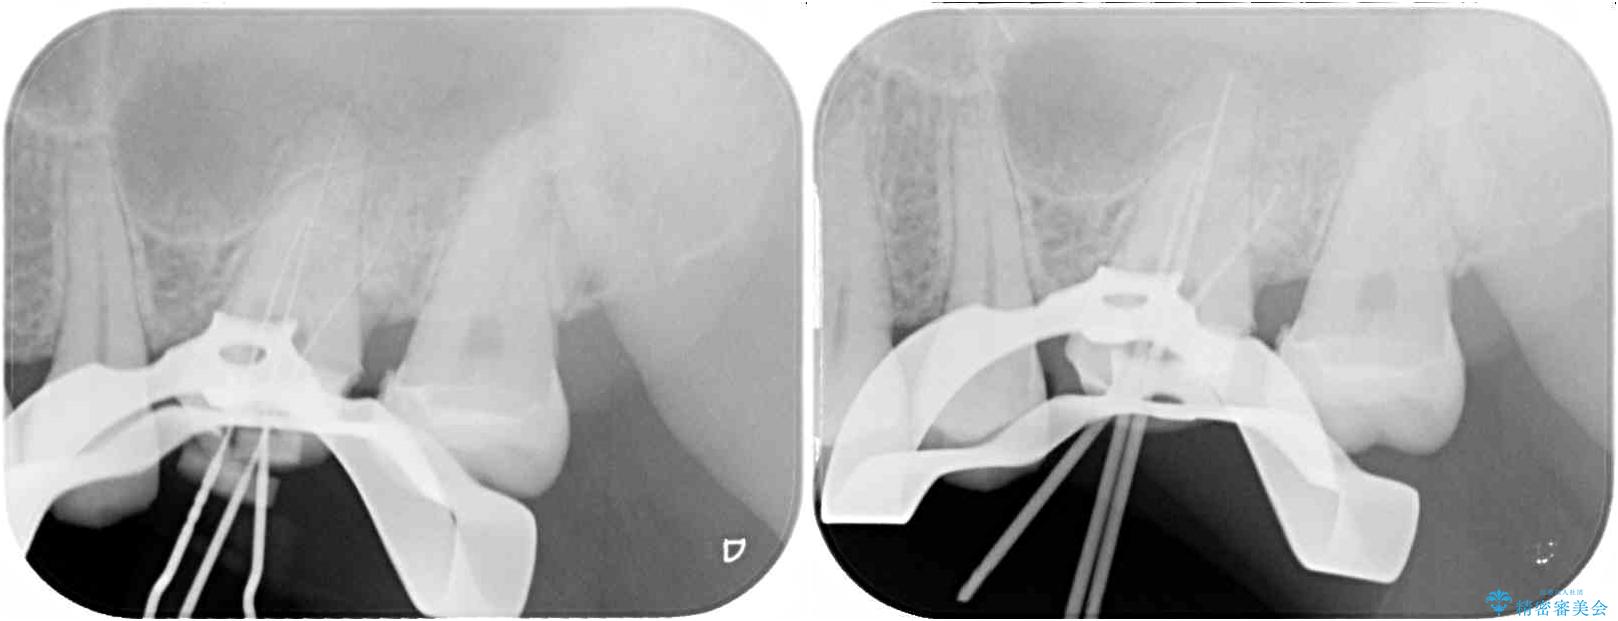

レントゲン写真から、神経組織近くにまで大きな修復物が認められました。

叩いたり、冷熱や電気刺激によるテストを行ったりとしましたが、炎症の状態は芳しくなく、根管治療を行う前提で処置を行うこととしました。

治療途中

• 奥歯がズキズキと痛む 奥歯の虫歯治療 治療途中画像